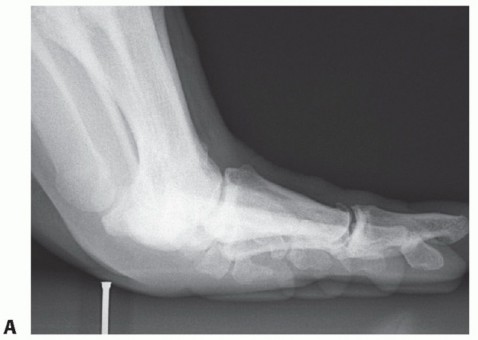

A thorough radiographic evaluation is mandatory (including weight-bearing views of the foot in the

anteroposterior [AP], lateral, and oblique planes) (FIG 3). Sesamoid axial views may also be helpful. Bilateral standing AP views are mandatory for comparison. Sesamoid station is assessed.

Forced (stress) dorsiflexion lateral views are helpful to diagnose disruption/diastasis of a bipartite sesamoid or a sesamoid fracture (FIG 4). It will also suggest a complete distal disruption of the FHB if the sesamoid(s) fails to migrate distally with dorsiflexion of the hallux. Studies suggest that more than 10.4 mm from the tip of the tibial sesamoid to the phalanx or more than 13.3 mm from the fibular sesamoid equates to a 99.7% chance for

plantar complex rupture.11 Compare the injured to uninjured side.

FIG 3 • A. AP foot radiograph showing proximal migration of the tibial sesamoid suggestive of an unstable turf toe injury. B. AP foot radiograph showing a hallux MP dislocation with an associated sesamoid fracture. C. AP radiograph demonstrating diastased bipartite tibial and fibular sesamoids. The proximal poles of each sesamoid are retracted.

FIG 4 • Dorsiflexion stress lateral radiographs. A. Normal. Note the position of the sesamoids. B. Abnormal. Note the proximal migration of the sesamoid complex.